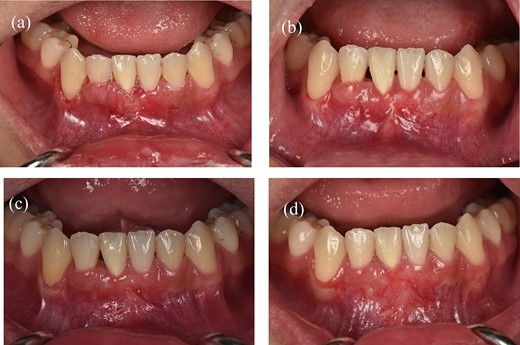

Clinical images of postoperative follow-up. (a) 3 weeks. (b) 2 months. (c) 6 months. (d) 12 months.

Results of treatment after one year of follow-up. (a) Intraoral image illustrating the labial view. (b) Intraoral image illustrating the lateral view. (c) Intraoral image illustrating the bird’s-eye dental view. (d) CBCT radiograph capturing the recession region.

In this case report, we discussed a technique for managing severe gingival recession after orthodontic treatment. The presented technique has consistently shown root coverage in the treatment of single deep narrow recession. Further investigation through ongoing research and comparative clinical studies will be essential to confirm these clinical observations. However, more research work and long-term follow-up will be needed to confirm the effectiveness.